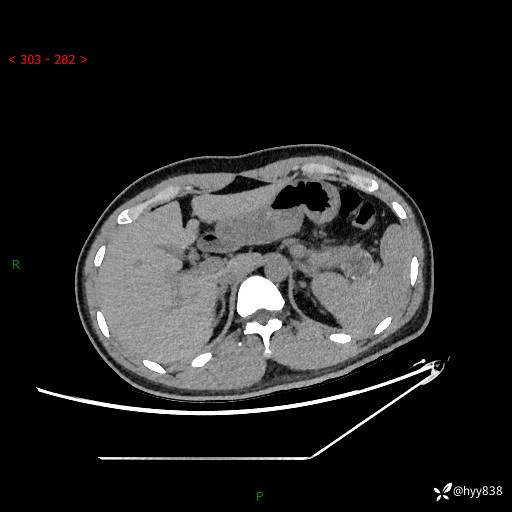

【患者信息】:31岁/男

【主诉】:间断性左下腹疼痛10天

【现病史及既往史】: 患者10余天前无明显诱因出现左下腹部疼痛,呈间断性,无恶心,呕吐,无黄疸,腹泻症状,于当地医院就诊,行腹部C提示:胰腺尾部占位。2型糖尿病。现患者为求手术治疗,门诊以“胰腺肿物”收入院。 患者起病来,一般情况可,大小便正常,体重体力未见明显减轻。

【检查】:胰腺CT平扫+增强